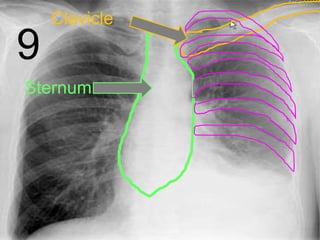

• Your skeletal system surrounds your most

important internal organs with a rib cage.